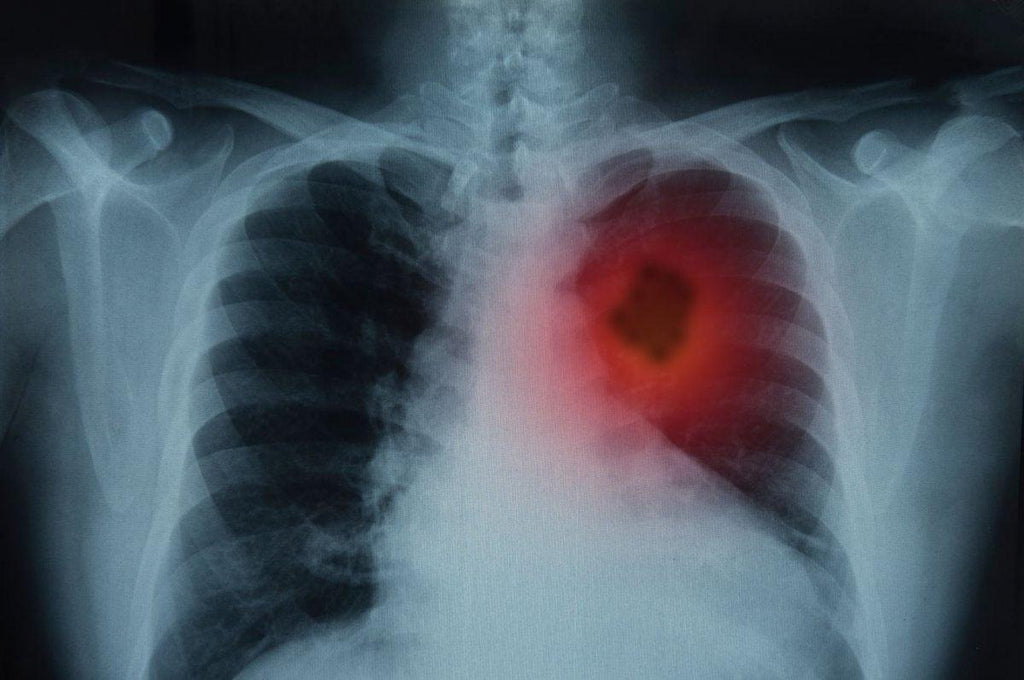

Don’t take your lungs for granted!

As much as I wish I could say otherwise, the inspiration for today’s blog comes from two people who are very dear to me. One who smoked for the better part of 50 years or more, and one who was successfully treated for breast cancer, only to learn that it had metastasized to her lungs. And watching both of them—one on oxygen 24/7 and the other undergoing lung cancer treatment—I have been starkly reminded...